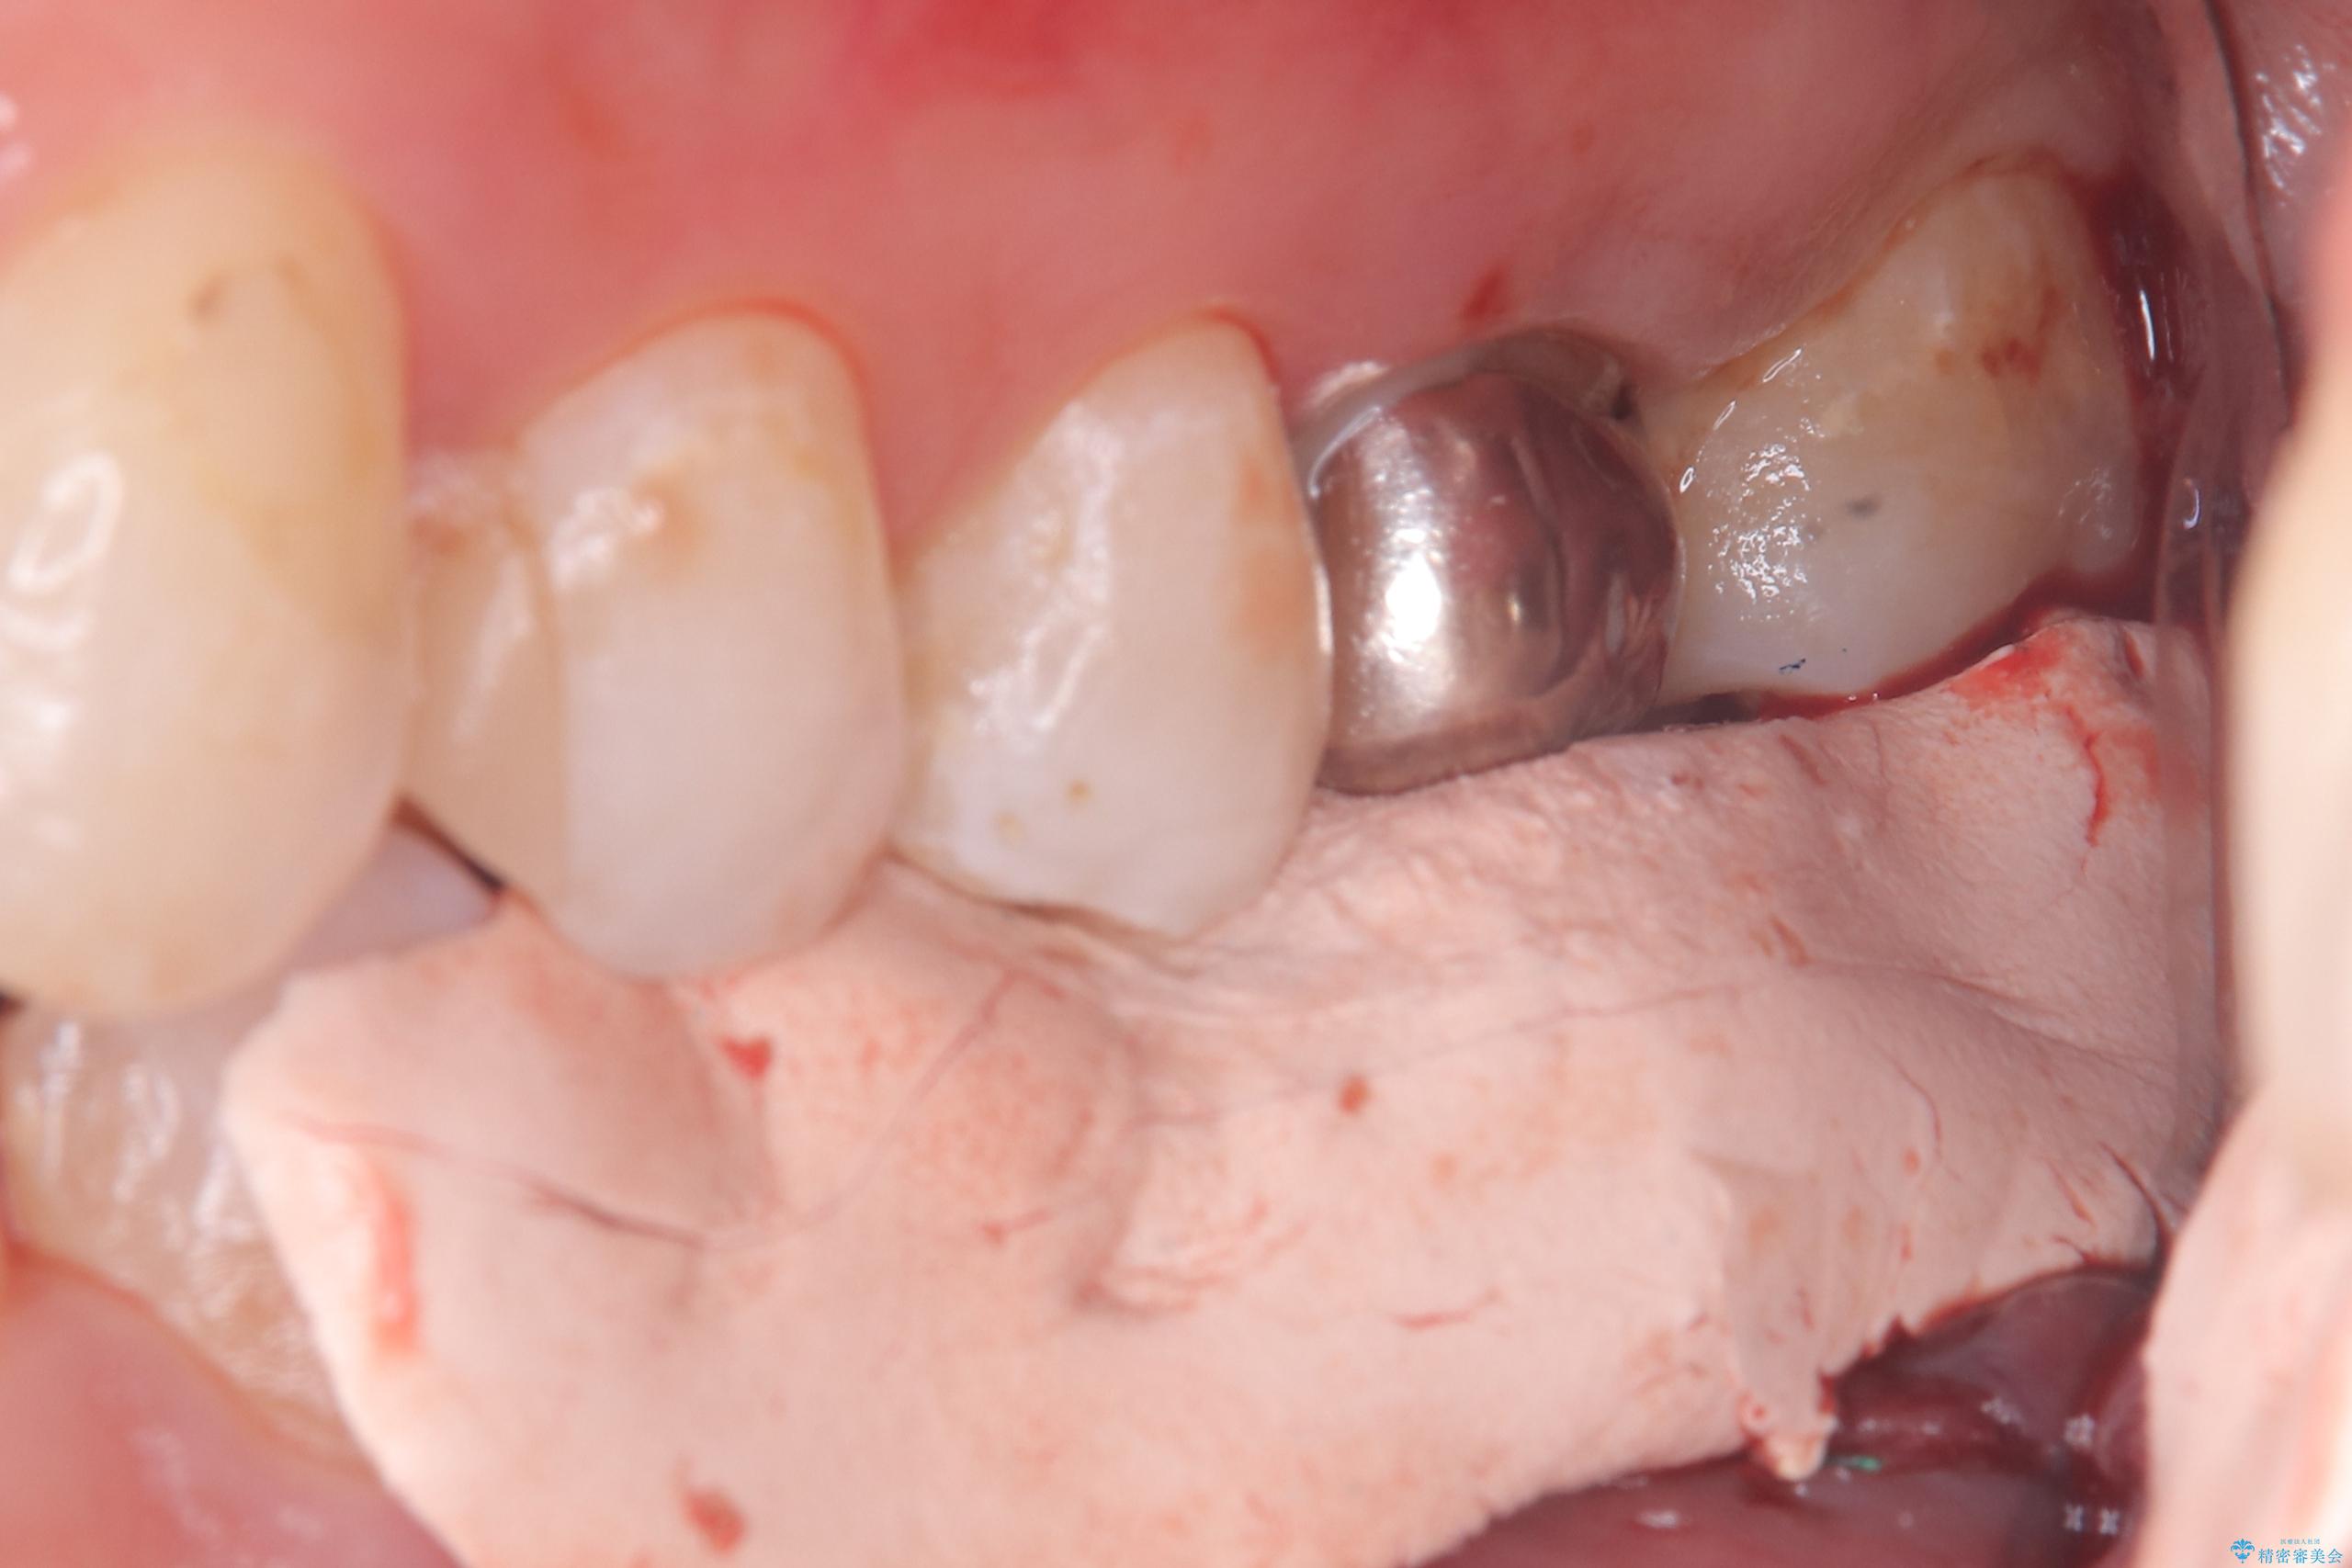

- 主訴:左下6番目の歯の周りが痛くなり、他院で診てもらったが抜歯と言われてしまった。ネットで歯牙移植というものを知りやっている医院を探している。

左下6番目の歯の周りに大きく透過像を認め、再根管治療後の予後が良くない可能性が大きく当院でも抜歯適用歯と説明しました。欠損部に対しインプラント治療や歯牙移植(左下の親知らずの移植)、ブリッジを提案し、歯牙移植を行うこととなりました。

保存が難しい左下6番目の歯を抜歯し、左下8番目の歯(親知らず)を抜歯窩に移植しました。歯牙移植後の動揺防止のため暫間固定を行っています。